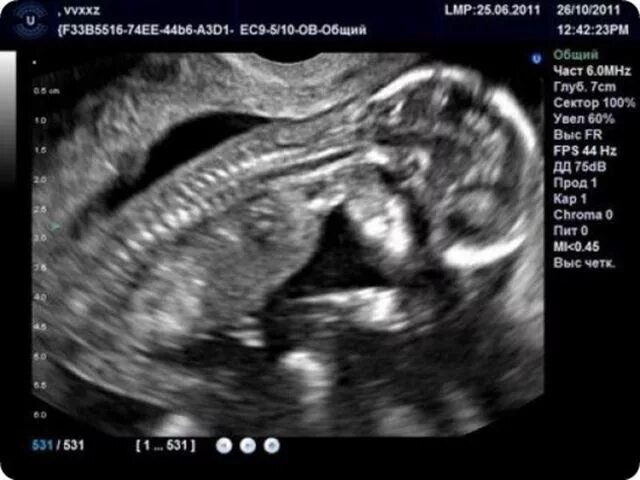

Беременность 15 недель развитие плода и ощущения